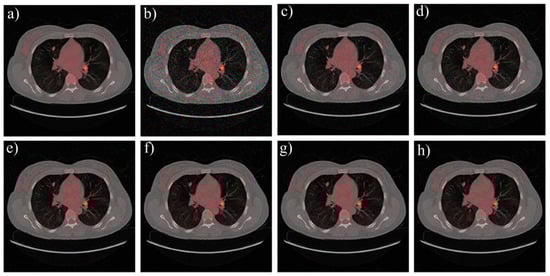

| Image | Algorithm | SNR (dB) | Time (s) | Memory Usage (MB) |

|---|---|---|---|---|

| CT | MP | 26.30 | 46.58 | 65.76 |

| OMP | 26.19 | 43.72 | 60.58 | |

| BP | 28.32 | 78.33 | 101.75 | |

| FAL0 | 33.19 | 10.79 | 22.37 | |

| AL0 | 34.01 | 22.24 | 36.68 | |

| AL0-L | 32.17 | 15.76 | 33.52 | |

| Fundus | MP | 27.52 | 44.57 | 68.32 |

| OMP | 26.88 | 42.16 | 61.07 | |

| BP | 29.11 | 81.15 | 112.59 | |

| FAL0 | 33.12 | 11.70 | 20.45 | |

| AL0 | 33.45 | 21.12 | 37.95 | |

| AL0-L | 32.77 | 15.69 | 36.58 | |

| Lena | MP | 28.22 | 49.02 | 68.70 |

| OMP | 27.73 | 46.33 | 59.42 | |

| BP | 29.45 | 85.19 | 127.34 | |

| FAL0 | 33.20 | 11.15 | 26.82 | |

| AL0 | 31.54 | 23.56 | 38.96 | |

| AL0-L | 32.54 | 18.77 | 35.40 |